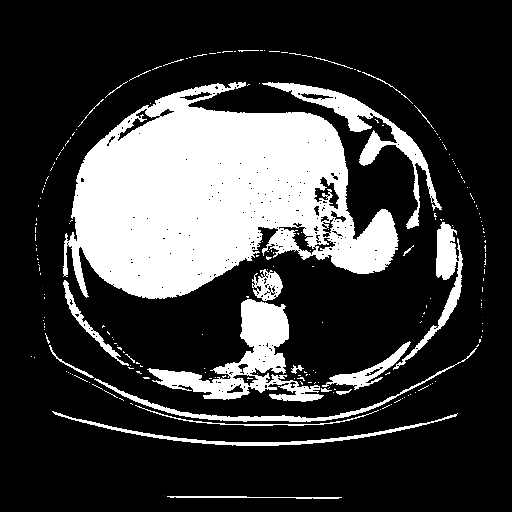

Image Grid

4Γ—3 grid: Rows show different image types (Original NATIVE, Reconstructed NATIVE, Original VENOUS, Generated VENOUS), Columns show windowing techniques (No Window, Lung Window, Mediastinum Window)

Generated VENOUS CT scan (A→B translation)

Full window (WL 1023.5, WW 4095 β†’ Low βˆ’1024, High +3071)

Actual HU range: [-1024.0, 3071.0]

Lung window (WL -600, WW 1500 β†’ Low βˆ’1350, High +150)

Actual HU range: [-1350.0, 150.0]

Mediastinum window (WL 40, WW 400 β†’ Low βˆ’160, High +240)

Actual HU range: [-160.0, 240.0]